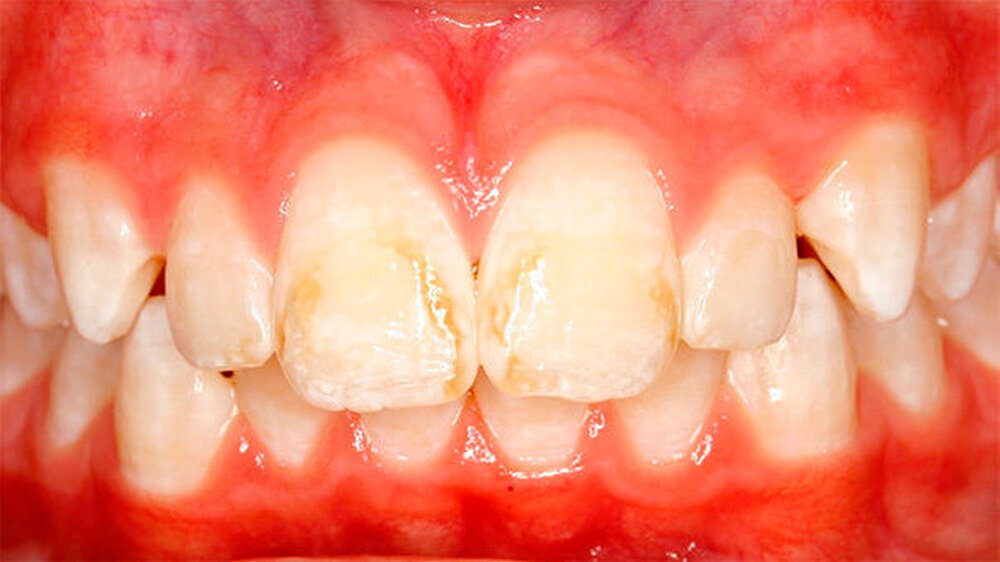

Bei einigen Patienten bestand allerdings auch schon im Milchgebiss eine Neigung zu Hypomineralisationen (Abbildung 3), klassifiziert wurden diese inzwischen als MDH (=deciduous molar hypomineralization) [Elfrink et al., 2012]. Inwiefern eine Hypomineralisation im Milchgebiss aber tatsächlich einen Indikator für eine MIH im bleibenden Gebiss darstellt, ist bisher nicht genauer zu beschreiben [Elfrink et al., 2012].